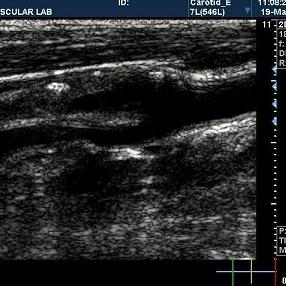

颈动脉图像

一种基于超声颈动脉图像的内中膜自动分割方法